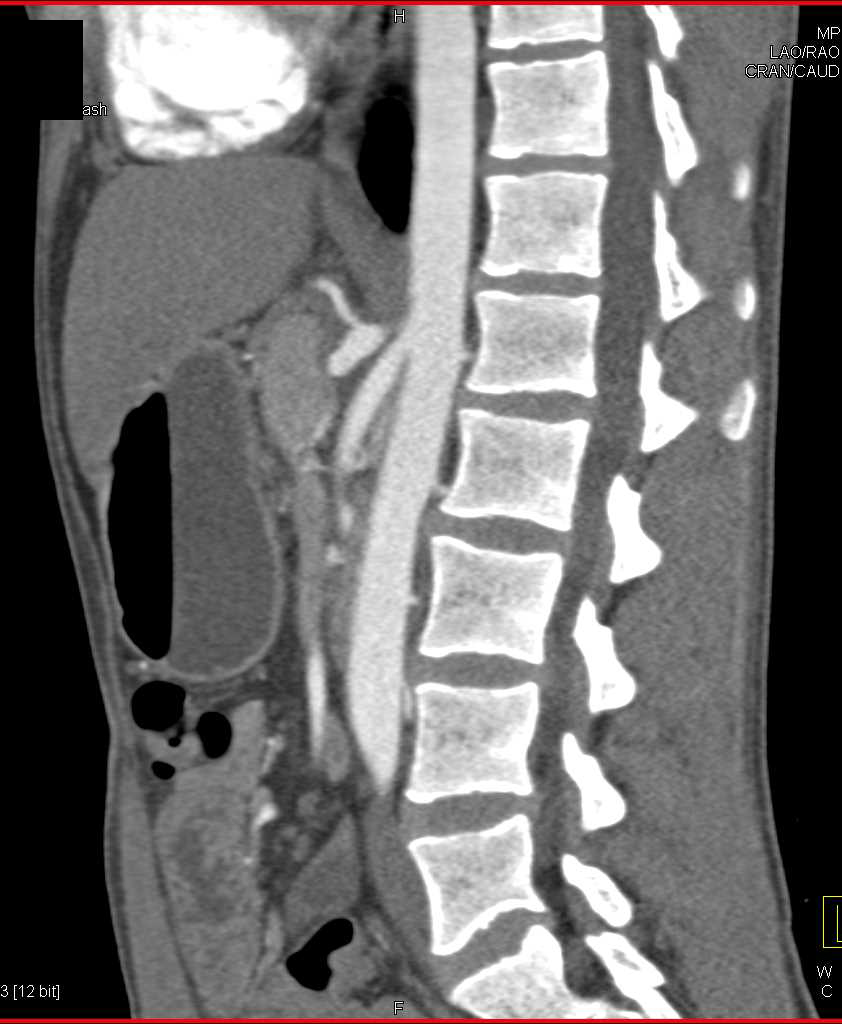

Carcinoid Tumor in the Root of the Mesentery with Vessel Encasement